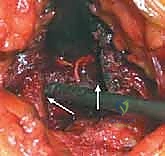

يمكن للجراح أخذ الطعم العظمي من جزأين رئيسيين في الحرقفة، ويتم اختيار الموقع بناءً على وضعية المريض أثناء الجراحة (على بطنه أم على ظهره) ونوع وكمية العظم المطلوب:

2. التشريح الخلفي لحرقفة الحوض (Posterior Iliac Crest)

يُعد الجزء الخلفي من الحرقفة هو الموقع الأكثر شيوعاً واستخداماً لأخذ الطعوم العظمية، خاصة في جراحات دمج الفقرات القطنية والصدرية حيث يكون المريض مستلقياً على بطنه (Prone). يتميز هذا الموقع بأنه يوفر كميات هائلة من العظم الإسفنجي عالي الجودة، بالإضافة إلى إمكانية أخذ طعوم قشرية كبيرة.

- المعالم العظمية الرئيسية: النقطة البارزة هنا هي الشوكة الحرقفية الخلفية العلوية (PSIS)، والتي تظهر غالباً كغمازة أسفل الظهر فوق الأرداف. المنطقة الممتدة للأمام وللخارج من هذه الشوكة هي بنك عظمي ممتاز.

- المخاطر العصبية والوعائية الدقيقة:

- الأعصاب الألوية العلوية (Superior Cluneal Nerves): هذه الأعصاب مسؤولة عن الإحساس في الجلد فوق الأرداف. تعبر هذه الأعصاب حافة الحوض على مسافة تتراوح بين 6 إلى 8 سنتيمترات بعيداً عن خط الوسط لجسم الإنسان. لتجنب قطع هذه الأعصاب (والذي يسبب تنميلاً مزمناً أو ألماً عصبياً في الأرداف)، يحرص الأستاذ الدكتور محمد هطيف على ألا يتجاوز الشق الجراحي واستخراج العظم مسافة 8 سم من الشوكة الحرقفية الخلفية العلوية.

- الثقبة الوركية الكبرى (Greater Sciatic Notch): تقع أسفل الشوكة الحرقفية الخلفية. يمر عبرها العصب الوركي (Sciatic Nerve) والشريان الألوي العلوي (Superior Gluteal Artery). النزول بعمق كبير أثناء أخذ العظم قد يهدد هذه الهياكل الحيوية، مما قد يسبب نزيفاً حاداً يصعب السيطرة عليه أو إصابة عصبية كارثية. لذلك، يتم أخذ العظم دائماً من المنطقة العلوية الآمنة.